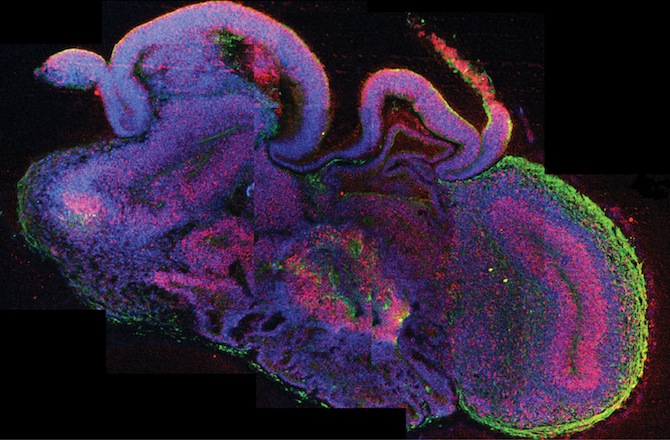

Juergen Knoblich, an author of the study, calls the tissue “cerebral

organoids,” and they can be cultured for months, eventually growing into

whole sections of the brain like the cerebral cortex or portions of the

hindbrain.

Although the brain cells can and will be used for diverse experiments, Knoblich and his team are focusing on replicating the causes and consequences of brain diseases or disorders like microcephaly, a condition of the head having a smaller circumference than the mean.

These cerebral organoids are a huge advantage for neuroscience researchers. Many experiments with the brain are done using mice or rats, but these animals are not a perfect simulation of how a human brain reacts to disease or disorder. With the organoids, scientists can achieve a simulation of a human brain and eliminate animal testing all together.